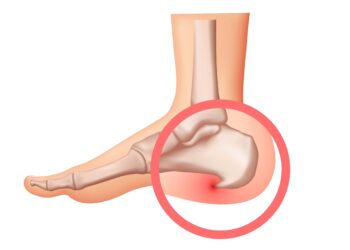

Skaityti daugiauDetailsKaulinės išaugos kulne, dar vadinamos kulno ataugomis, dažnai susiformuoja ilgainiui ir daugelis žmonių apie jas net nesužino, kol nepradeda varginti...

Skaityti daugiauDetailsKulnies riebalinio sluoksnio atrofija – tai būklė, kai sumažėja ar suplonėja apsauginis riebalinis audinys po kulno kaulu. Šis sluoksnis veikia...